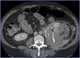

Dilated calyx

Renal ultrasonography (Renal US) is the examination of one or both kidneys using medical ultrasound. Ultrasonography of the kidneys is essential in the diagnosis and management of kidney-related diseases. [Source: Wikipedia ]